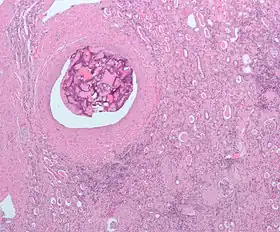

| Micrograph of embolic material in the artery of a kidney. The kidney was surgically removed because of cancer. H&E stain. | |

An embolism is the lodging of an embolus, a blockage-causing piece of material, inside a blood vessel.[1] The embolus may be a blood clot (thrombus), a fat globule (fat embolism), a bubble of air or other gas (gas embolism), amniotic fluid (amniotic fluid embolism), or foreign material.

An embolism can cause partial or total blockage of blood flow in the affected vessel.[2] Such a blockage (vascular occlusion) may affect a part of the body distant from the origin of the embolus. An embolism in which the embolus is a piece of thrombus is called a thromboembolism.